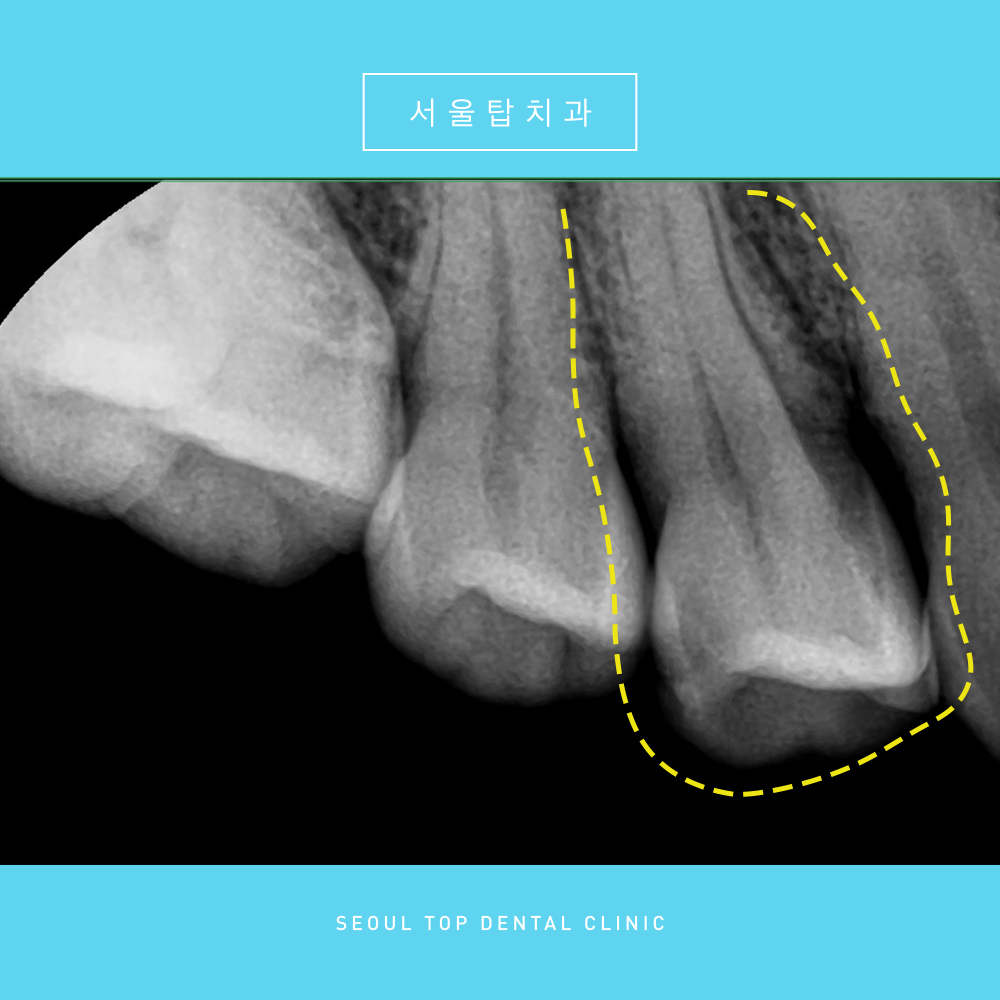

더욱 정밀한 체크를 위해,

해당 치아를 면밀하게 확인할 수 있는

치근단 사진을 촬영해보았는데요.

첫번째 작은어금니에 깊은 충치로 인해

충치치료가 필요하였습니다.

인레이가 가능하면 인레이로 치료해보려 했으나,

충치 부위를 제거해보니

방사선상 소견보다 실제 충치가 더욱 깊어

신경치료가 불가피한 상황이었습니다.